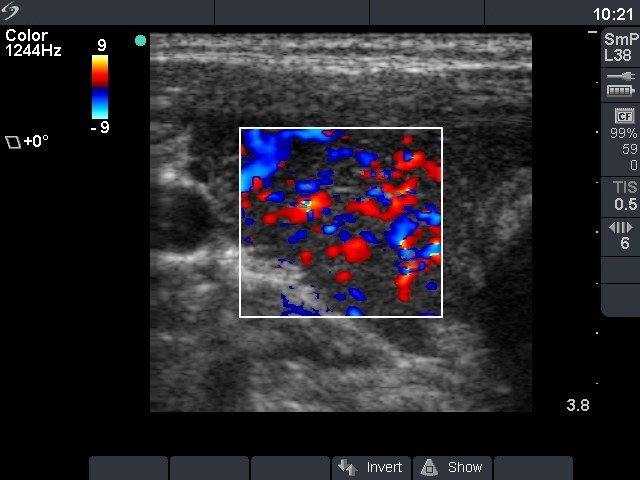

First investigation 6 months after delivery (first and second rows of images)

Ultrasonography: the thyroids were hypoechogenic without any nodule. The vascularization was increased.Cytology resulted in Hashimoto's thyroiditis.